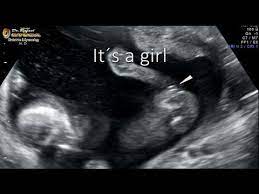

What Does Dating Scan Mean - Early Pregnancy Scan Dating Scan Safehands Medical Centre : The only stuff that relates to the baby itself are fhr (foetal heart rate or the babys heart beat) and crp (crown to rump length used in dating the baby).. A difference in age in your first trimester could indicate two things:. First trimester dating is the most accurate way to estimate your baby's due date. What does the conception + 2 weeks mean? Present on a variety of business and office printers, scanning is a function that digitizes printed documents and pictures and sends the files to your computer or outputs a duplicate copy of the items via the printer. If your baby is moving around a lot, or if you're overweight or obese, it can be more difficult for the sonographer to get a good view of your baby.

The phrase 'dating' is extremely common, and so is the grey area that tends to follow it around. Having the scan does not hurt, but the sonographer might need to apply slight pressure to get clear views of your baby. In a fertile menstrual cycle of 32 days, ovulation would occur on cycle day 18. During a dating scan, your sonographer will also check that the embryo has implanted in your uterus (womb). If your baby is moving around a lot, or if you're overweight or obese, it can be more difficult for the sonographer to get a good view of your baby.

If my hcg levels haven't significantly increased then it will mean the pregnancy isn't 'viable'. A dating scan is an ultrasound scan to determine how many weeks pregnant you are and your due date. A dating scan shouldn't hurt, but sometimes the sonographer does have to press quite hard on your tummy, which can be a bit uncomfortable, and may leave you with a few bruises. This is called the dating scan. Dating scans during pregnancy | june 2018 this written information is for guidance only and does not replace consultation and advice by your health care provider. A difference in age in your first trimester could indicate two things:. 'is a scan that uses sound waves to create a picture. Do scans not go from conception + 40 weeks?

It's used to see how far along in your pregnancy you are and check your baby's development. The dating scan usually takes about 20 minutes. Purpose of the pregnancy dating scan. This is because the scan measures the size of your baby. The dating scan can include a nuchal translucency (nt) scan, which is part of the combined screening. This is an ultrasound scan that is performed early in the pregnancy. Nearly all scans after 10 weeks can be done through your tummy, and most units ask you to arrive with a full bladder. Continue to look at their picture until you find one attractive feature. A dating scan is an ultrasound scan to determine how many weeks pregnant you are and your due date. Listen, i don't want to say that dating includes having sex. #4 it can include sex. This gives the most accurate estimation of the baby's age, based on development. The clerk of usps scans the bar code of the mail and updates the status of the package at the usps system, then sends it to its next destination.

It checks if the fetus is growing normally and has any congenital abnormalities. I will keep you posted on how things go, thanks again smile. If it has implanted outside your uterus, it's called an ectopic pregnancy, which is a medical emergency. Other information obtained includes whether the pregnancy is in the uterus or outside the uterus (an ectopic pregnancy), how many embryos there are, and. Though 28 days is called average, 32 days is closer to average length. Posted tuesday 04 december 10:51am. This is an ultrasound scan that is performed early in the pregnancy. A dating scan is in fact more accurate the earlier it is done. 'is a scan that uses sound waves to create a picture. When i went for my dating scan, at 12+6, the sonography didnt say anything to me about my baby, she just said i was around 13weeks. You know, catch a glimpse of who they are. It is also known as a 'anomaly scan' or an '18 to 20 week scan'. During a dating scan, your sonographer will also check that the embryo has implanted in your uterus (womb).